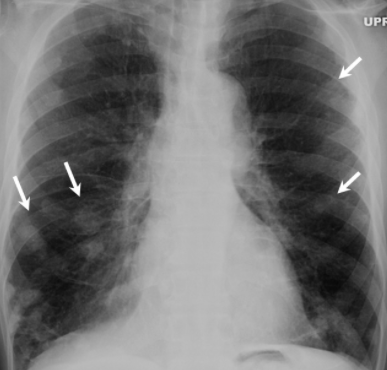

RX

- Nodules nécrobiotiques avec cavitations et prédominance sous-pleurale

- Plutot petits-moyens en taille (contrairement DD: Wegener)

- Complications: Pneumothorax